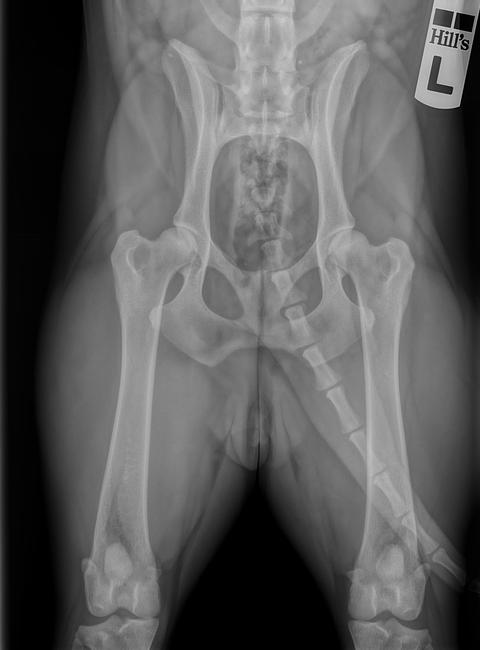

Gisteren ben ik naar de dierenarts geweest om mara haar heupen op de foto te laten zetten.. aangezien ik graag verder wilde in de behendigheid leek me dat een strak plan.. ook mara's broer heeft hd..

en ja hoor.. ik zag het meteen al (ik mocht mee de rontgen kamer in en Mara zelf vasthouden) dat de heupen er niet al te goed uitzagen..

De dierenarts classificeerde het tot een hd-b/hd-c. Behendigheid kon nog, zolang ik maar voorzichtig deed met de A-schutting enz.

Ten eerste vind ik de foto's slecht genomen.

Op de 1e foto ligt de hond niet recht, de knieschijven zijn niet mooi naar voren gedraaid.

Hierdoor lijkt het erger dan het is.

Wel is duidelijk te zien dat de rechterheup (op de foto links) de kom minder diep is dan de linker kant.

Ook de 2e foto is vreemd genomen waardoor een vertekend beeld te zien is.

Mag ik vragen waar je de foto's hebt laten nemen?

Is het door een DA gedaan die verstand heeft van het maken van heupfoto's?

En hoe komt hij aan HD-B/HB-C?

Alleen het beoordelingsteam van de raad van beheer kan jou de juiste uitslag geven, een DA doet vaak een suggestie, maar die kan er net zo goed naast zitten.

Ik snap dat je baalt, maar als het daadwerkelijk HD-B is is het nog niet zo slecht, honden die HD_B hebben hebben geen last van de heupen en er kan nog gewoon mee gefokt worden, of je dit van plan bent doet er niet toe, maar het is om even aan te geven dat HD-B geen slechte heupen zijn.

Als ik jou was (maar dat is mijn mening) zou ik de foto's op nieuw laten maken en dit keer een DA uitzoeken die geen roesje gebruikt, heupen die op de foto zijn gezet onder een roesje zullen altijd anders o de foto staan, de roes zorgt er namelijk voor dat het lichaam en de spieren slap zijn en daardoor kan de hond scheef op de foto liggen en de benen niet in de juiste (normale) stand hebben staat en dus een vertekend beeld geven.

Even als voorbeeld, dit is de HD foto van mijn teef, met beoordeling HD-A.

Ik vind de foto inderdaad ook niet echt super genomen, maar goed, je kan wel zien dat er speling zit tussen de kommen en de koppen, wat wijst op HD.